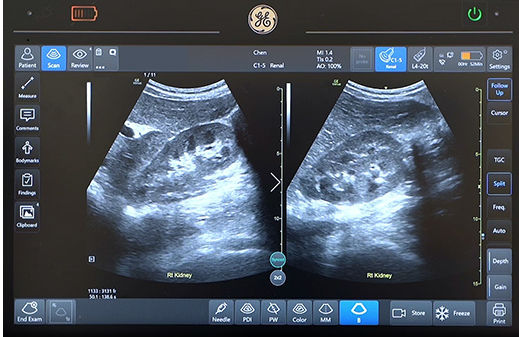

Quickly assess kidneys and the bladder with Renal Diagram

Simplify documentation and provide easy follow up for patients with suspected hydronephrosis. No need to type findings; simply assign a label from a pre-populated list that correlates with images.

renal-diagram-review-desktop cropped